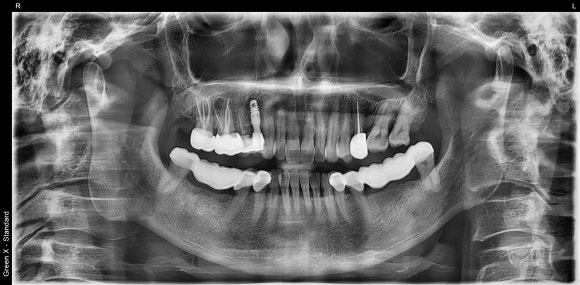

20241014

우리 치과에서 충치 치료를 받고 계시던

아름다운 미모의 50대 환자분이십니다.

20241230

오른쪽 위 작은 어금니에 탈이 났습니다.

더 이상 치료를 할 수 없는 상황이라

부득이하게 발치를 권해드렸습니다.

20240120

치아를 둘러싼 염증이 심하신 편이 아니어서

(=깨끗하고 감염이 없는 뼈조직)

치아를 발치하면서 동시에

임플란트를 식립하였습니다.

뼈가 얇고 좁은 환자분들은

시간이 지남에 따라 뼈가 흡수되어

주저앉는 경우가 많기 때문입니다.

수술 후 반드시 CT를 촬영하여

원하는 위치에, 원하는 방향으로

임플란트가 제대로 식립되었는지

확인하는 것이 중요합니다.

눈으로 볼 수 없는 곳까지

꼼꼼하게 체크하는 과정입니다.

임플란트를 원하는 위치에 정확히 식립하는 것은

술자의 경험과 공간지각력에 의해

크게 좌우됩니다.